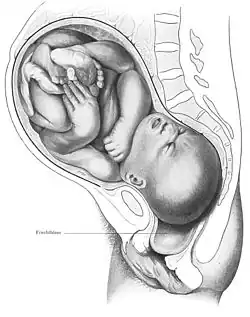

Die das Kind umgebenden Eihäute werden Fruchtblase genannt. Diese kann sich entweder vor Wehenbeginn oder in jeder Geburtsphase öffnen (Blasensprung). Sehr selten bleibt die Fruchtblase bei der Geburt des kindlichen Kopfes intakt. Man spricht dann von einer „Glückshaube“.

Die normale Geburt (auch Spontangeburt) des Menschen beginnt mit der Eröffnungsphase, dem ersten Stadium der Geburt. Sie beginnt meist mit unregelmäßigen Wehen mit einer Frequenz von 2–3 Wehen in 30 Minuten. Ziel der Eröffnungswehen ist die Verkürzung der Cervix uteri (Gebärmutterhals) und die Erweiterung des Muttermundes. Im Verlauf der Eröffnungsphase erhöht sich die Wehenfrequenz normalerweise langsam bis auf 2–3 Wehen in 10 Minuten. Auch der Rhythmus wird meist regelmäßiger. Die Dauer der Wehen in der Eröffnungsphase beträgt durchschnittlich 60 Sekunden. Eine Geburt ist allerdings ein sehr individueller Vorgang, weshalb Wehen in Abstand, Dauer und Intensität und damit auch die Geburtsdauer sehr unterschiedlich sein können. Das Eröffnen der Fruchtblase verstärkt manchmal die Wehen.

Der kindliche Kopf wird bei normalem Geburtsverlauf gebeugt. Während der Kopf den Beckenboden überwindet und austritt, geht er in eine Überstreckung über. Ist der Kopf geboren, tritt normalerweise eine Wehenpause ein und mit der nächsten Wehe macht das Kind wieder eine Drehung um 90°, schaut also dann wieder nach rechts oder nach links, damit die Schultern aus dem längsovalen Beckenausgang austreten können. Sind die Schultern geboren, folgt der Rest des kindlichen Körpers unmittelbar.